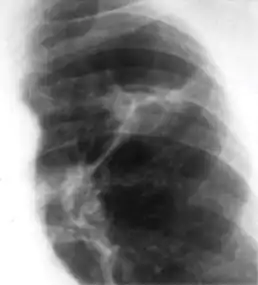

3. Nodule with poorly defined margins - Round density within the lung parenchyma, also called a tuberculoma. Nodules included in this category are those with margins that are indistinct or poorly defined (tree-in-bud sign[3]). The surrounding haziness can be either subtle or readily apparent and suggests coexisting airspace consolidation.

Chest x-ray showing nodule with margins that are indistinct or poorly defined (tree-in-bud sign) in post-primary pulmonary TB.